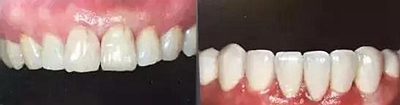

上下前牙正面影像

構(gòu)圖包含4-6顆前牙,中切牙為對焦中心

采用黑背景

拍攝比例:1:1.8,光圈f38,快門速度1/125,閃光強(qiáng)度M/4

上下前牙側(cè)面影像